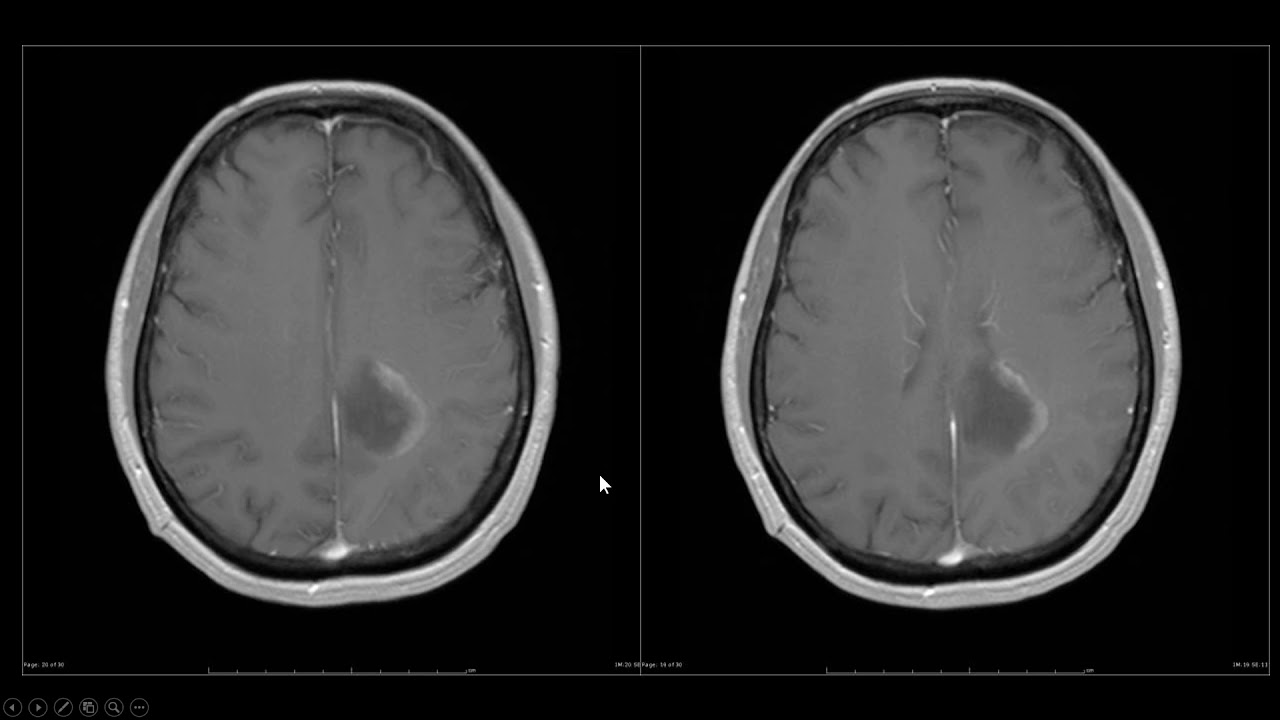

também tem por exemplo doenças que vão pegar neurônios que tem mielina só do sistema nervoso periférico só nervo por exemplo a síndrome de guillain-barré por exemplo e a gente tem doenças que pegam só mielina de neurônios do sistema nervoso central como por exemplo a esclerose múltipla a minha Elite transversadistrofias e muitas outras então eu vou colocar aqui a listinha nas doenças desdemenizantes do sistema nervoso central do sistema nervoso periférico a gente ainda tem uma doença desmenizante que pega o neurônio do sistema nervoso central e periférico no caso da esclerose lateral amiotrófica por exemplo nós temos